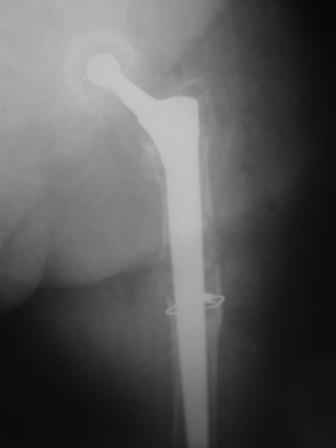

You transformed a cemented hip prosthesis to a cementless revision hip prosthesis with a little approach.

* your nail has a point of minus resistance at the tip of femural stem and at the fulcrum of the fracture; by the time could it break?

* by the time stem and nail could reciprocally move?

* distal fixation of the nail is based near only on two screws : are they sufficient to secure a good stability before fracture consolidation?

* materials of the stem and nail (I think Iron steel in both); if they should be different (and many hip prosthesis are made by an alloy that is not the same of the nails) we could see electrolytic phenomena

I generally should prefer a long stem revision prosthesis, as that allegated.

The nail tip is jammed. Since it is conical, it can only be jammed more with axial load.

I'd say yes because we use same 6 mm screws for femoral nailing and allow immediate weight-bearing regardless of fracture pattern.

The nail is Ti-based alloy.